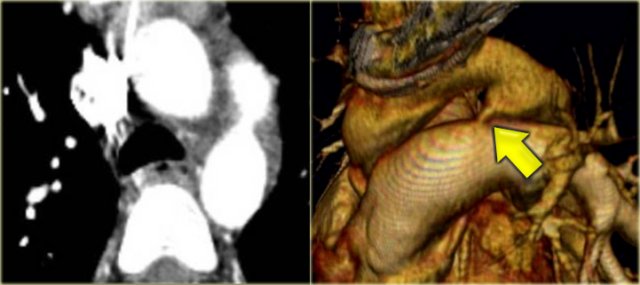

Right Arch with Aberrant left subclavian

On the left a patient with a right arch with an aberrant left subclavian (indicated by the yellow arrow).

Scroll through the images on the left.

Again you have to realize that the axial CT-images have a 'view from feet'.

Which vessels are indicated by the yellow and green arrow?

There is a right arch and the left subclavian artery is the last branch of the aortic arch, indicating that this is an aberrant left subclavian.

Medially to the left subclavian artery we see the left common carotid, that originates from the right side and has an oblique course to the left.

The yellow arrow indicates the azygos vein.

The green arrow indicates the left superior intercostal vein, a normal variant, that we will discuss later.

Posterior oblique view: Right Arch with Aberrant left subclavian (yellow arrow) Posterior oblique view: Right Arch with Aberrant left subclavian (yellow arrow)

Same patient.

Posterior oblique view of volume rendered image to show the aberrant left subclavian artery.

In a mirror type right arch, the left subclavian is the first brach and forms the left innominate together with the left common carotid.

Right Arch with Aberrant left subclavian Right Arch with Aberrant left subclavian

On the left images of a symptomatic child.

On the axial image there is a right arch with the left subclavian artery that comes off on the posterior side and runs behind the trachea and the esophagus.

The compression of the trachea is demonstrated on the volume rendered view.